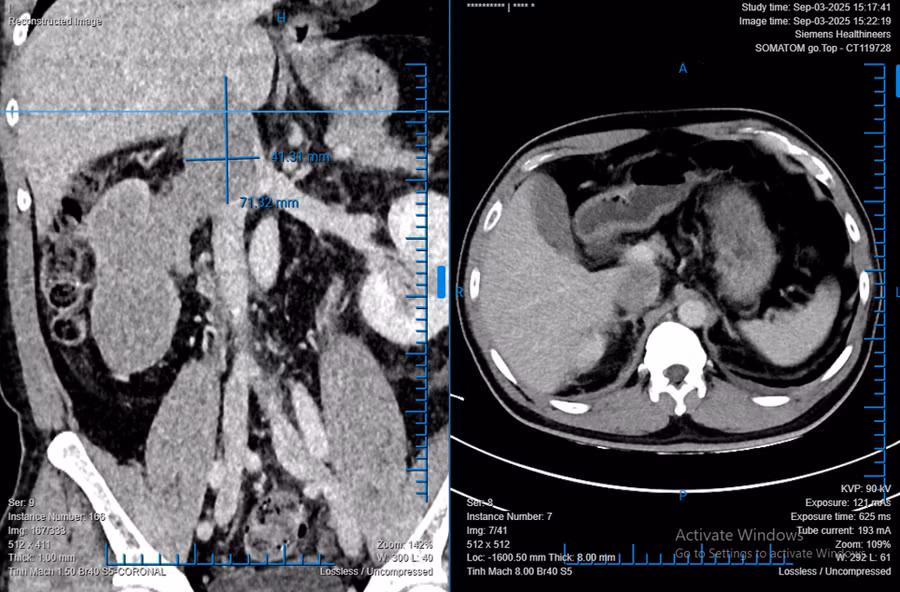

Bệnh nhân L. phát hiện khối bướu thận khổng lồ trong lần khám sức khỏe định kỳ. Kết quả chẩn đoán hình ảnh cho thấy khối bướu chiếm gần toàn bộ thận phải, kích thước lên đến 138mm và có huyết khối bướu lan sâu vào tĩnh mạch chủ dưới. Nếu không can thiệp kịp thời, tính mạng người bệnh bị đe dọa do nguy cơ thuyên tắc phổi và suy tim.